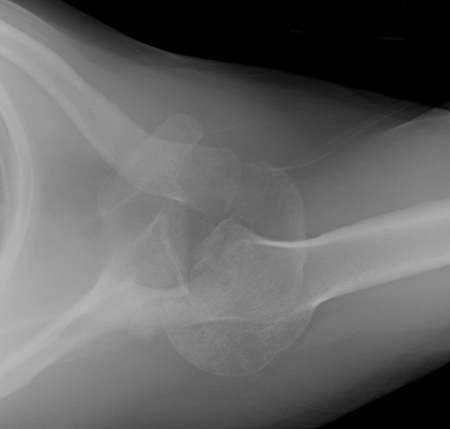

Visão lateral de radiografia de luxação posterolateral do cotovelo

Acervo pessoal do Dr. Paul Novakovich